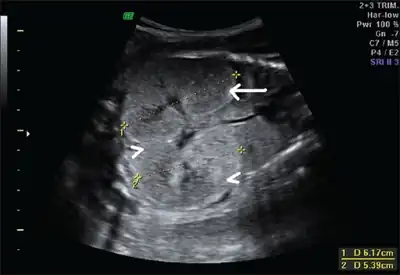

Ultrasonography is the primary method to evaluate autosomal recessive polycystic kidney disease, particularly in the perinatal and neonatal stages.[3]